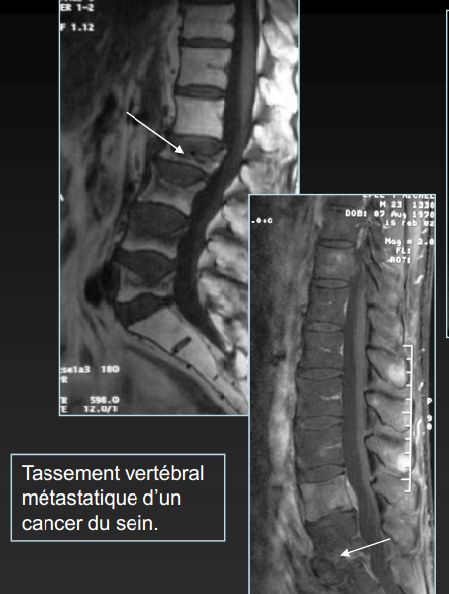

10. Ung thư di căn cột sống

- Đau lưng kéo dài, không đáp ứng thuốc giảm đau

- Đau tăng về đêm

- Sụt cân, mệt mỏi không rõ nguyên nhân

Hình ảnh xẹp đốt sống thắt lưng và chèn ép tủy sống do ung thư di căn

Cảnh báo: Cần phát hiện sớm để tránh liệt và biến chứng nặng.